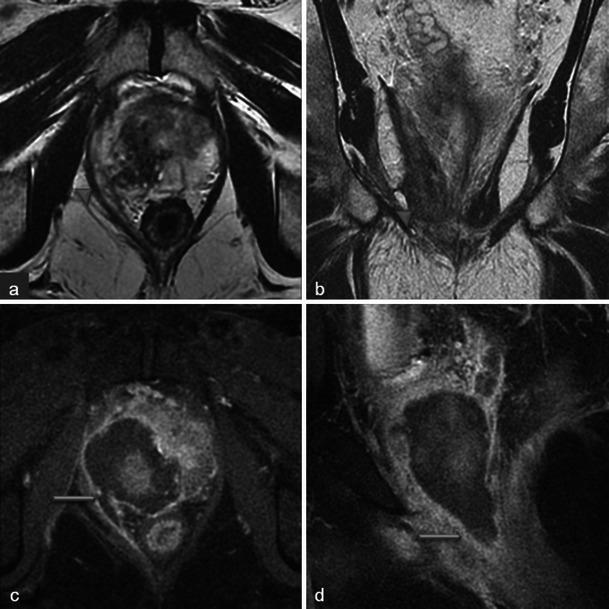

In this technique, a photosensitising agent is introduced intravenously, then activated by local laser illumination to induce tumour necrosis. Treatment efficacy is assessed by magnetic resonance imaging (MRI).

We illustrate specific post-treatment MRI aspects at early and late follow-up with pathological correlations.

• Dynamic phototherapy is a new and promising focal therapy for prostate cancer. • One-week MRI shows increased volume of the treated lobe and large, homogeneous necrosis area. • Six-month MRI shows significant changes of the prostate shape and signal. • Six-month MRI becomes "base line" appearance for further follow-up or monitoring.

• 动态光动力疗法是一种用于前列腺癌的新型且有前景的局部治疗方法。• 一周后的MRI显示治疗叶体积增大以及大片均匀的坏死区域。• 六个月后的MRI显示前列腺形态和信号有显著变化。• 六个月后的MRI成为进一步随访或监测的“基线”表现。